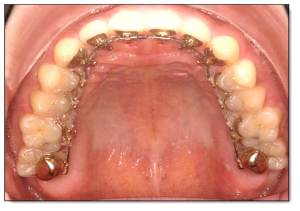

4. 美國原廠製作完成您專屬的矯正器與矯正線後,再寄送至矯正醫師,依治療計畫,按時為您配戴和治療(圖三)。

圖三 A,3M Incognito舌側矯正口內觀